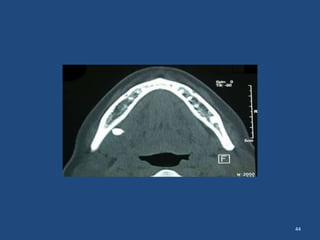

Displacement of the root

-into the soft tissues

OPT showing displaced right

mandibular molar root in the

submandibular space

44